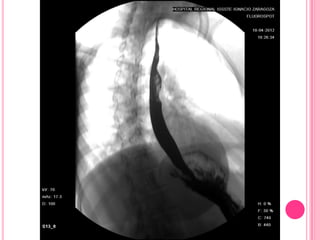

El estudio baritado muestra un esófago dilatado por alteración del peristaltismo y

falta de relajación del esfínter esofágico inferior, que presenta el típico aspecto en

"pico de flauta" (flechas)